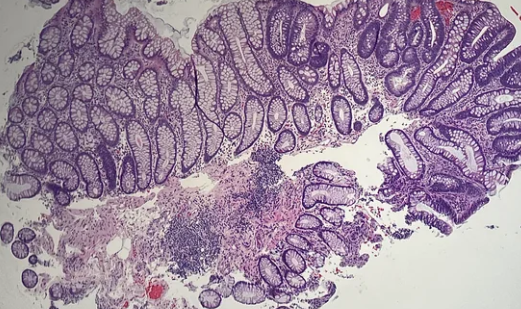

관상 선종은 대장 점막의 선세포가 비정상적으로 증식해 생기는 선종성 용종입니다.

- 용종(폴립) → 장 점막이 혹처럼 튀어나온 모든 병변

- 선종 → 그중에서 암으로 발전 가능성이 있는 조직

👉 모든 용종이 선종은 아닙니다.관상 선종은 선종 중에서도 가장 흔하고 비교적 위험도가 낮은 유형입니다.

선종의 종류와 암 위험도 차이

종류 특징 암 위험도 관상 선종 가장 흔함 낮음~중간 융모 선종 표면이 융모 형태 높음 관융모 선종 혼합형 중간~높음 크기와 조직 형태가 암 진행 위험도를 결정합니다.